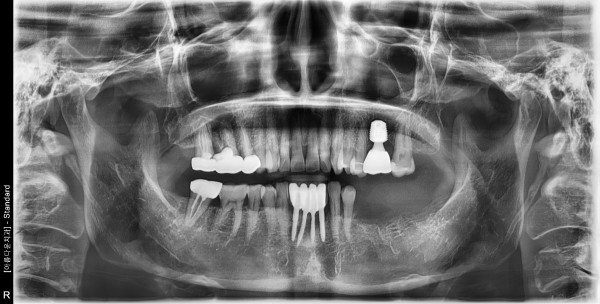

56세 여자환자 / 좌측구치&우측상악 발치후 뼈이식 및 임플란트 식립